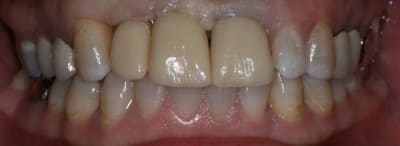

18/06/2011 à 23h17

On avance dans le cas, j'ai revu la patiente hier.

Elle est satisfaite et moi pas vraiment, comme quoi...

Elle ne veut pas faire de chir mucco gingivale et accepte éventuellement que je fasse une petite chir d'élongation coronaire sur 21 car elle trouve cela surperflux.

Tristesse et difficulté des sourires gingivaux !

J'avais bien raison de me méfier au départ...

Dommage pour la teinte...

Une greffe osseuse aurait bcp aider, les implants sont trop enfouis par rapport à la 21.

Je suis persuadé que si ton prothèsiste réussit à reproduire la richesse des petits défauts de ses propres dents sur tes dents en céramique , ce serait et ça passerait bcp mieux

Je crois que finalement ces trois trop jaune et quasi monolithique ds leur couleur est vraiment la chose la plus atroce

Entièrement d'accord avec vous...

Bon finalement je vous poste le cas terminé.

La prochaine fois je ferrai une greffe d'apposition comme j'avais pu le préssentir... Ca me permettra de garder les papilles.

A la prochaine séance je gomme la coloration mésiale de 12, c'est promis ;+)

Un cas pas évident... l'important est que la patiente soit contente à la fin.